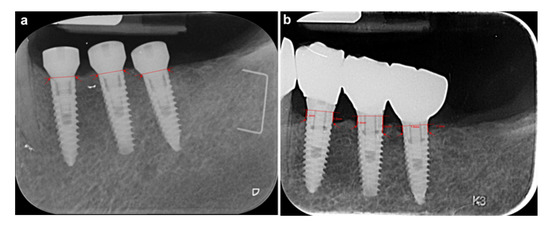

- Mesial and distal bone level were measured at T0 and Tf. (Figure 1a and Figure 1b, respectively). Radiographs were analyzed using a computer program (VixWin ProVrs. 1.5e Gendex Dental Systems. KAVO DENTAL 200 S Kraemer Blvd, Building E2 Brea, CA 92821). Analogue radiographs were digitalized with a flatbed scanner (Epson Expression 1680pro; Seiko Epson Corp.) with 600 dpi resolution and eight-bit grey values. The image files were stored as TIFF files and analyzed using the computer program VixWin on a 24’ flat screen (Philips 243V5Q, 1920 × 1080; Philips) in a particular room under exclusion of natural or artificial light except the screen. After calibration using the implant’s diameter, mesial and distal distances between implant shoulder and bone crest were measured using the ruler measurement tool. The degree of accuracy was 0.05 mm. A single trained and calibrated investigator (MS) performed the evaluation of all radiographs. Replicate measurements were done on 23 implants.